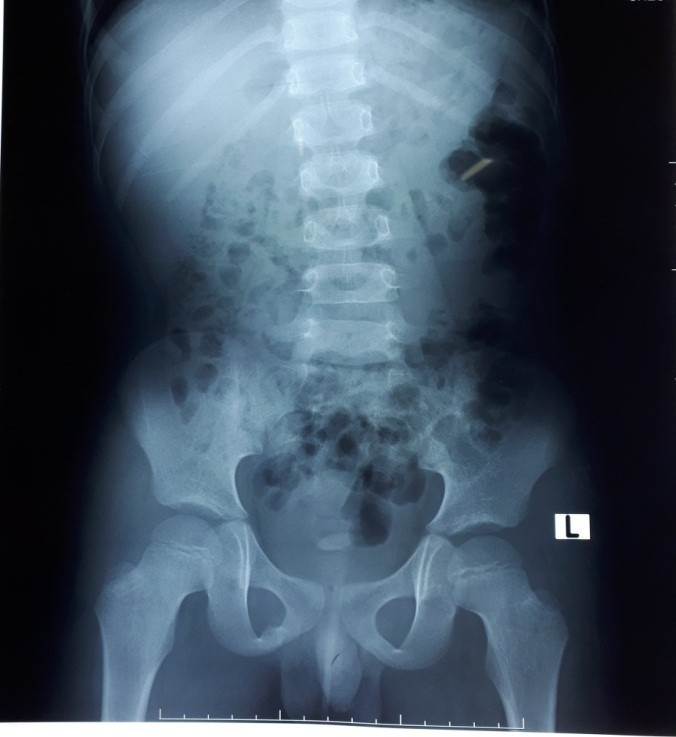

Qua thăm khám, làm siêu âm hệ niệu và X-quang bụng, các bác sĩ khoa Ngoại Thận – Tiết Niệu – Nam Học BVĐK Tỉnh Bắc Giang phát hiện nhiều viên sỏi ở cả hai thận kích thước nhỏ 3mm và có 01 viên sỏi bàng quang kích thước 10mm nằm sát cổ bang quang cản trở đường ra của nước tiểu đặc biệt ở tư thế đứng tiểu. Gia đình cháu L cho biết, rất ngạc nhiên vì nghĩ cháu bé như vậy thì không thể có sỏi thận được.

| Hình ảnh sỏi tiết niệu của bé Hoàng Viết L 8 tuổi trên phim chụp |